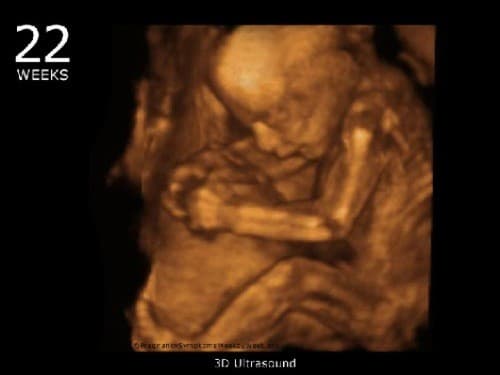

Đây là mốc siêu âm 3D, 4D quan trọng để bác sĩ chẩn đoán tình trạng thai nhi, khảo sát các dị tật thai, bởi lúc này bé gần như hoàn thiện nhưng chưa quá lớn để gây chật buồng ối. Nước ối của mẹ lại nhiều nên máy siêu âm dễ dàng quan sát hơn là ở những tuần sau.

Siêu âm thai tuần 22, bác sĩ sẽ kiểm tra:

– Đo chiều dài cơ thể và kiểm tra tứ chi xem thai có đủ 5 ngón không.

– Đo chiều dài của đầu, đường kính hộp sọ xem có bất thường không, đánh giá lượng chất lỏng trong não và hình dạng của tiểu não phía sau não bộ.

– Kiểm tra tim xem có đủ 4 ngăn không,Có nhìn thấy các động mạch không, Tim và dạ dày đúng vị trí không, Có hoạt động bình thường không,…

– Kiểm tra xương sống, đo theo chiều dài và tiết diện cột sống xem có đủ các đốt xương sống không và đã được sắp xếp thẳng hàng, có da bao phủ phía sau chưa.

– Kiểm tra cơ quan nội tạng như dạ dày, thận, bàng quang có hoạt động bình thường không.

– Kiểm tra nước ối, phát hiện được sự bất thường của nước ối và bánh nhau.

Từ những kết quả kiểm tra, có thể giúp cho bác sĩ có thể biết được thai nhi có bất thường gì không, có nguy hiểm gì không, chẩn đoán tình trạng thai, quan sát hình thái bất thường của thai như sứt môi, dị tật, hở hàm, dị dạng ở nội tạng, các chi, các bộ phận khác, phát hiện sự bất thường của bánh nhau, nước ối,… từ đó mà có những biện pháp xử trí thích hợp.